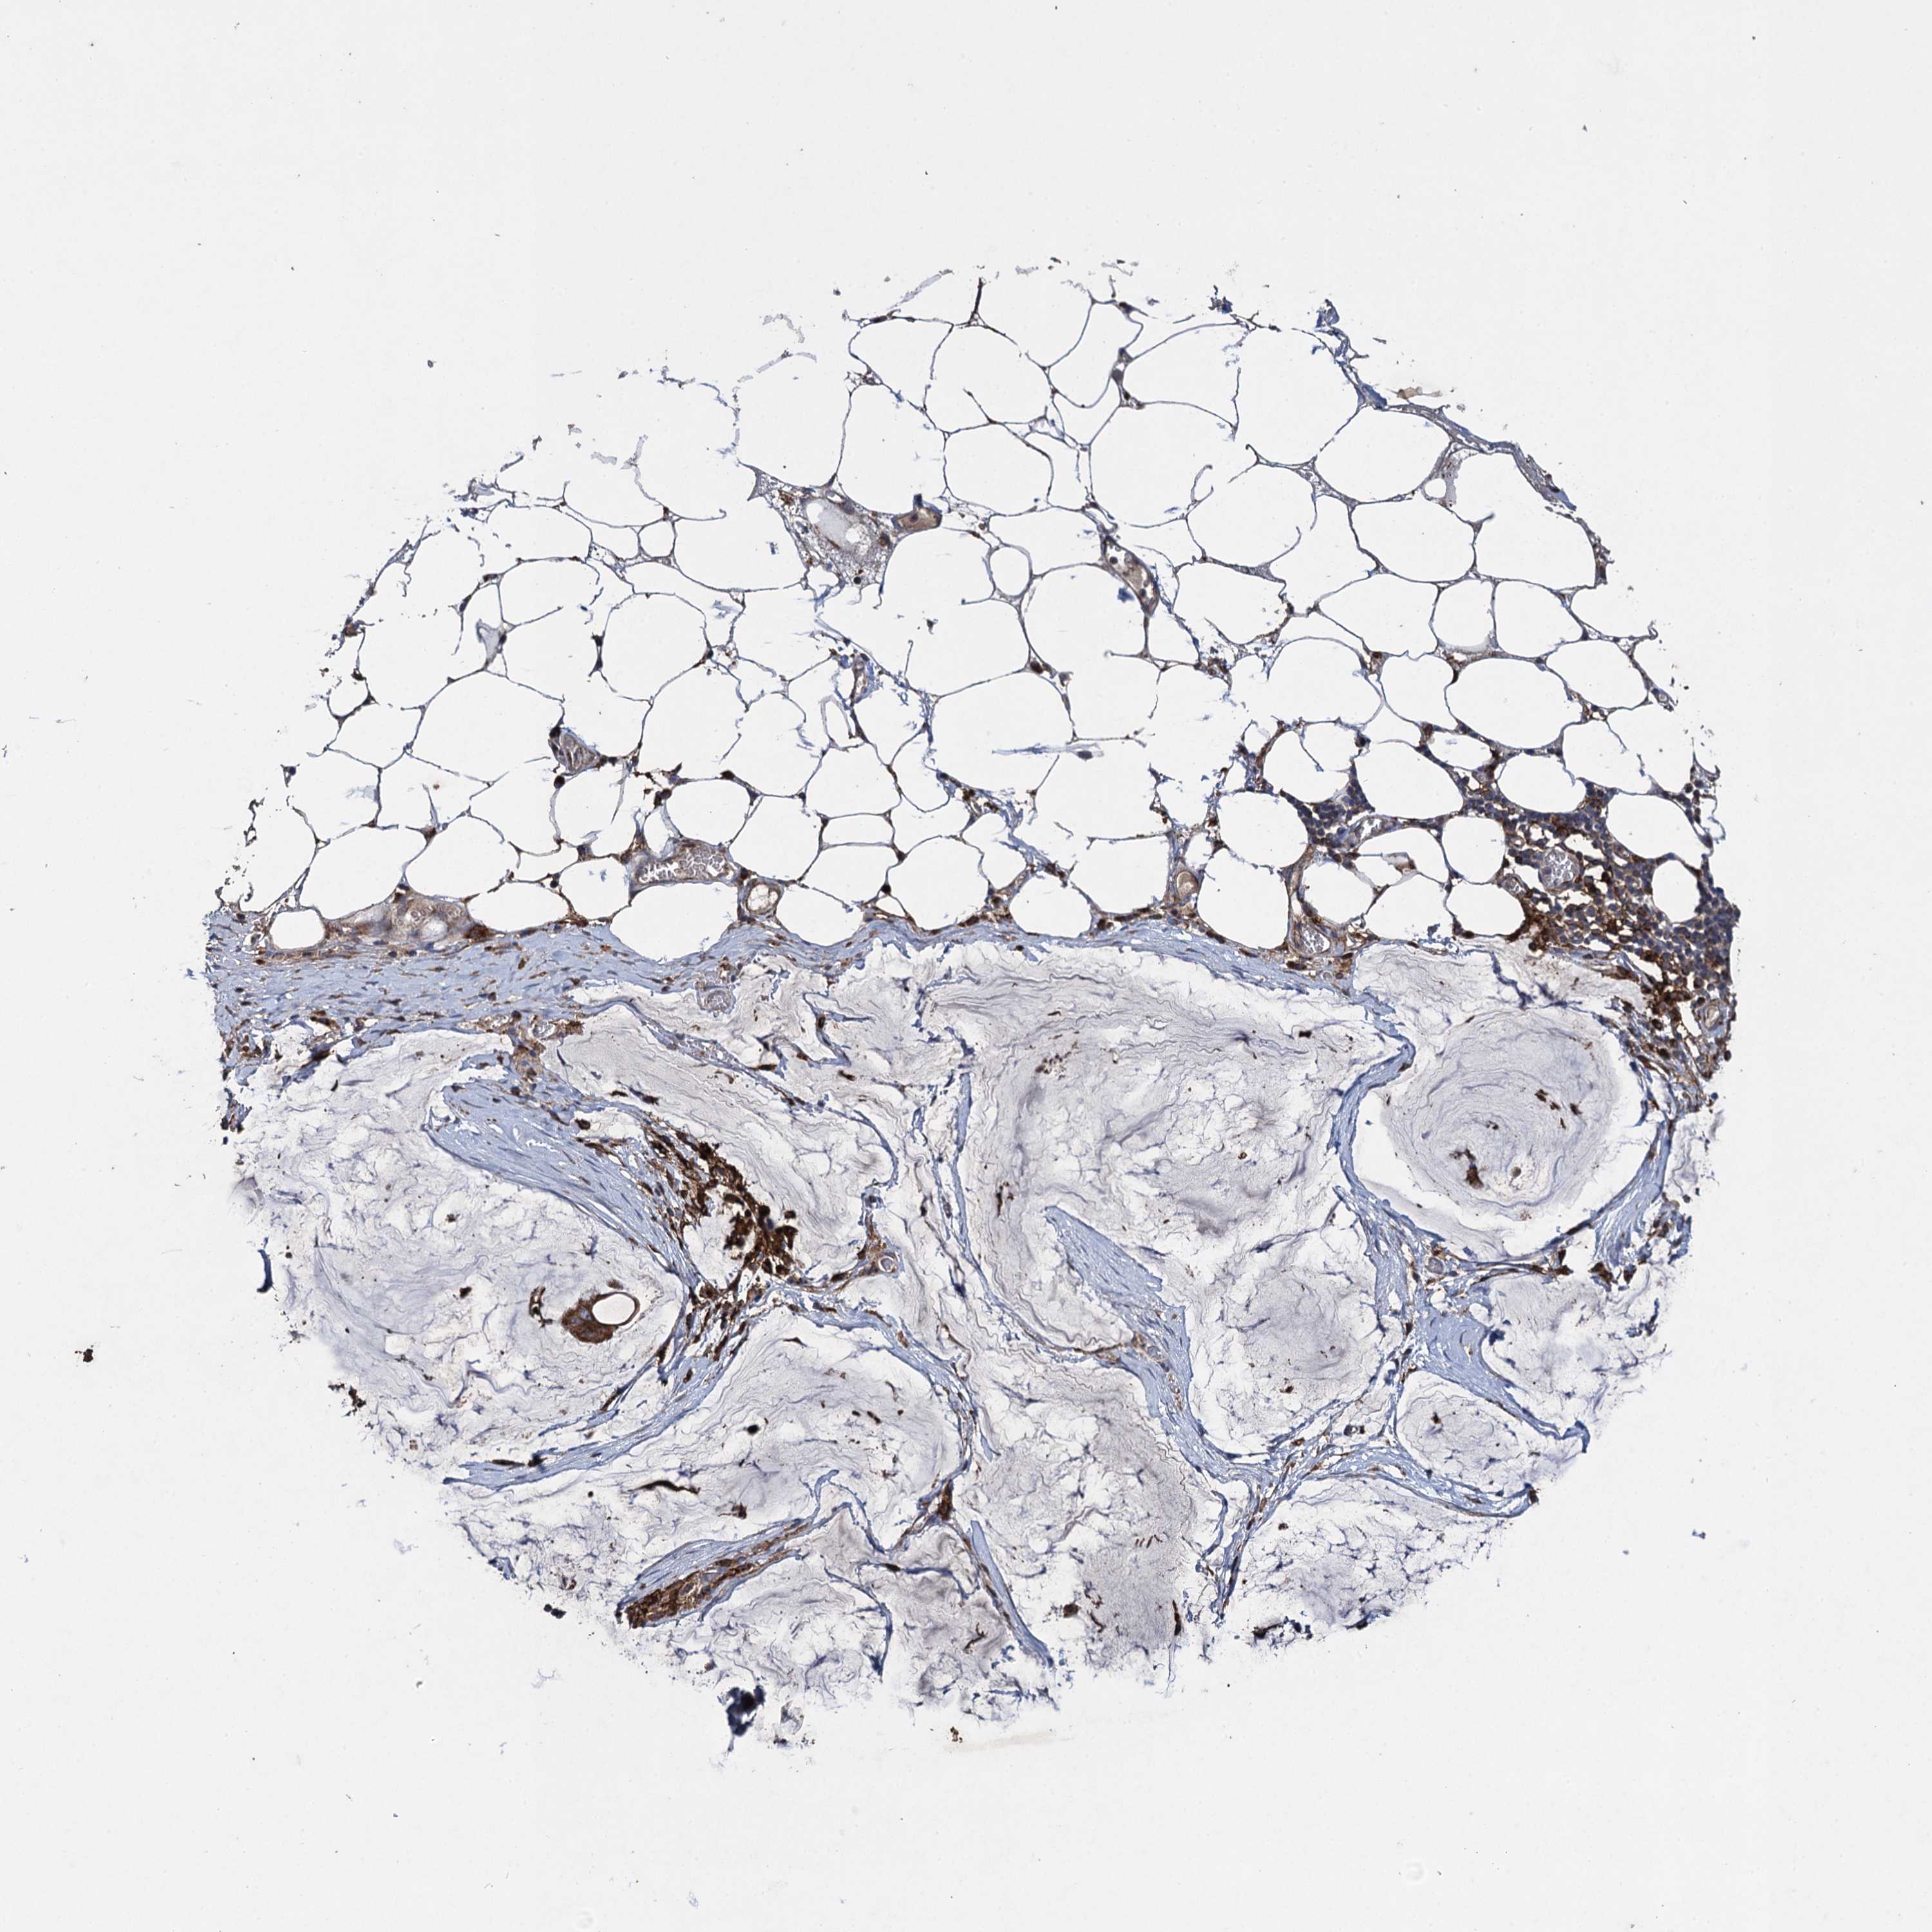

OVARIAN CANCER - Protein expressioni

A mouse-over function shows sample information and annotation data. Click on an image to view it in a full screen mode. Samples can be filtered based on level of antibody staining by selecting one or several of the following categories: high, medium, low and not detected. The assay and annotation is described here.

Note that samples used for immunohistochemistry by the Human Protein Atlas do not correspond to samples in the TCGA dataset.

Antibody stainingi

Antibody staining in the annotated cell types in the current human tissue is reported as not detected, low, medium, or high, based on conventional immunohistochemistry profiling in selected tissues. This score is based on the combination of the staining intensity and fraction of stained cells.

Each image is clickable and will lead to virtual microscopy that enables deeper exploration of all samples and also displays staining intensity scores, fraction scores and subcellular localization as well as patient and tissue information for each sample.

Antibody HPA041174

Antibody HPA041390

Cystadenocarcinoma, serous, NOS

Carcinoma, endometroid

Cystadenocarcinoma, mucinous, NOS

Carcinoma, NOS